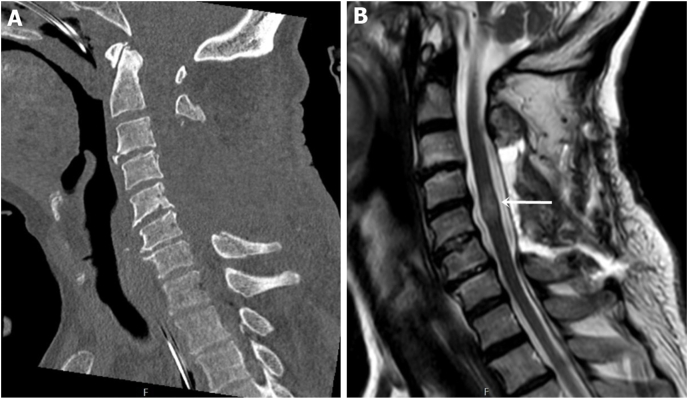

Case report: A 62-year-old male with a cervical spinal injury underwent emergency decompression at an external facility. Subsequent imaging revealed iatrogenic instability due to multi-level laminectomies (C3-C6). Preoperative CT data were processed using software (Mimics v14, MeshMixer) to design patient-specific templates, printed with a 3D Ultimaker 2 printer. These sterilized templates were used intraoperatively for navigation, aiding in transpedicular screw placement at C2, C7, and T1 levels, with lateral mass screws placed for C3-C6 using a freehand technique.

Results: Intraoperative fluoroscopy confirmed accurate screw placement with no vertebral artery injury or malposition. Postoperative CT validated precise alignment, and no hematoma or complications were observed. The use of 3D templates reduced operative time and radiation exposure compared to traditional methods.